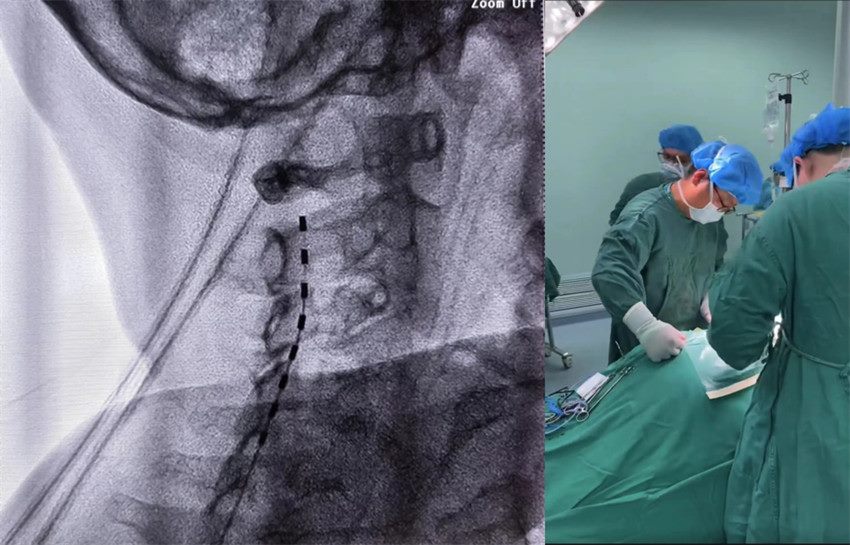

吴建珩主任团队决定实施一项前沿技术

脊髓电刺激术

这项技术在医院已成功开展多次

小琦目前的治疗条件也已具备

随后一期、二期手术顺利进行